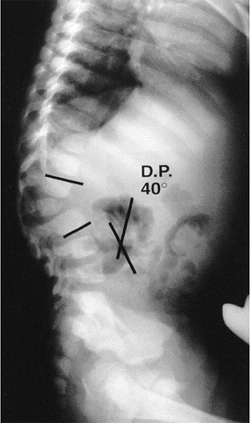

radiographs provide the most information in the evaluation of

congenital kyphosis (Fig. 20.8). Failure of

![]() |

|

Figure 20.8

A 2-year-old child with type I congenital kyphosis measuring 40 degrees. Radiograph demonstrates failure of formation of the anterior portion of the first lumbar vertebra. |